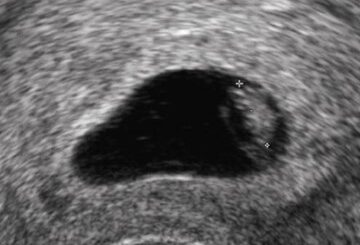

Quand se produit la fécondation après l’ovulation ?

Quand a lieu la fécondation ? On vous dit quand a lieu la fécondation après l’ovulation ainsi que de divers traitements naturels pour tomber enceinte mais aussi garder la grossesse à terme et accoucher...